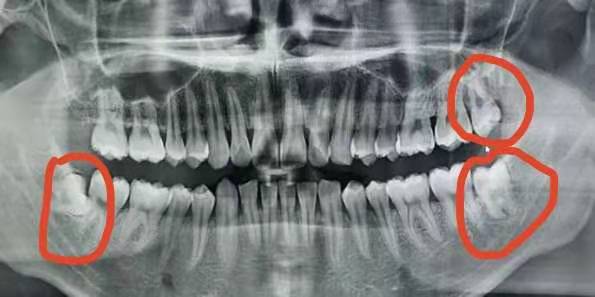

在X線片上可以看得很清晰:

我國16~25歲人群中智齒的萌出率為54%,在已萌智齒中阻生和錯位約占44% ,

其中發生在下頜者約是上頜者的2.5倍。